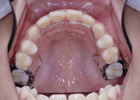

Q10.成人矯正はどんな器具で行われるのですか?

1.3D装置:

小さな顎を正しい大きさに拡大します。あるいは、奥歯の位置を固定します。

2.ブラケット:

歯に装置を接着して、ワイヤーを用いて歯並びを治します。

<表側矯正装置>

<裏側矯正装置>